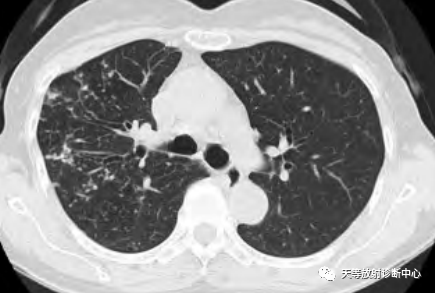

影像学表现:整体观察肺内多发病灶,散在分布,病灶的主要形态为:多发大小不等肺气囊、多发结节共同存在。

1、肺气囊大小不等,张力较大,圆形膨胀感强,周围可见大小不等结节影;

2、病灶主要沿支气管血管束方向分布,部分病灶达到胸膜下;

3、支气管间质增厚;

4、结节影大小不等,小的呈树芽征堆积,大的部分到达胸膜小,具有糊墙征,性格较温和。仔细观察病灶呈四边形、多边形,边缘刀切感,边界模糊。

首先感觉病变并不是非常的恶,偏向温和的病变。